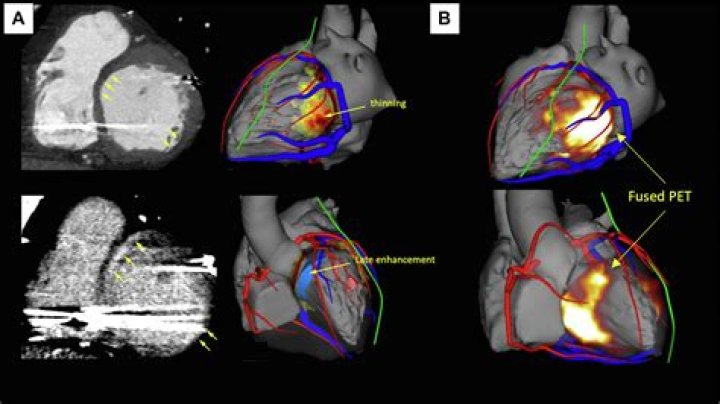

What does the delayed enhancement indicate on the cardiac MRI? Delayed enhancement identifies infarction or fibrotic tissue, while absence of enhancement ...